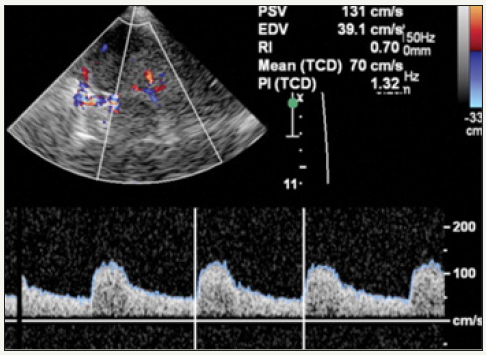

TCD relies on pulse wave Doppler to image a particular vessel and a received echo generates an electrical impulse which is processed electronically to produce a spectral waveform [8,9]. A spectral Doppler waveform is visual display of flow-velocities within a specific are of blood vessels as a time velocity curve. Spectral analysis can thus be use to estimate not only the blood flow velocity, it can also used to calculate the peak systolic (PSV) and end diastolic (EDV) velocities, systolic upstroke or acceleration time, pulsatility index (PI), resistive index (RI) and time averaged mean maximum velocity (V mean) (Figure 3). TCD devices are equipped with larger sample volume unlike the normal Pulse Wave Doppler (PWD) for other uses; this is to obtain better quality of signal in noisy background also. Standard TCD is recorded bilaterally using PWD for at least 10 cardiac cycles [10].

Figure 4: Duplex Doppler image and spectral waveform show the velocity of blood flowing within the PCA. The PSV, EDV, MFV, and resistive index (RI) are automatically calculated from the waveform.